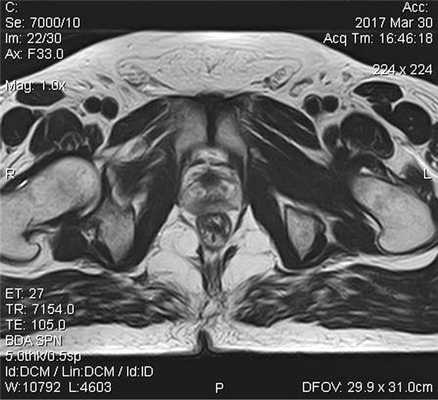

Пациент С., 1945 года рождения, считает себя больным с 2012 г., когда впервые отметил затруднения при мочеиспускании, однако к врачам не обращался. В июле 2016 г. при плановом обследовании по месту жительства выявлено повышение ПСА до 276 нг/мл, выполнена трансректальная биопсия предстательной железы под ультразвуковым контролем. Больной для дальнейшего обследования и лечения обратился в поликлинику МНИОИ им. П.А. Герцена. При гистологическом исследовании, пересмотре стекол и блоков гистологических препаратов в МНИОИ им. П.А. Герцена выявлен инфильтративный рост ацинарной аденокарциномы 7 (4+3) баллов по Глисону, занимающей до 80% площади биоптатов. Пациент самостоятельно выполнил ПЭТ/КТ с холином. По данным ПЭТ/КТ, в обеих долях простаты определяются очаги накопления радиофармпрепарата (РФП) неоднородного характера, с наиболее выраженным накоплением РФП до макс. SUV 12,09 в периферической зоне слева и переходных зонах предстательной железы с обеих сторон (рис. 1), Рис. 1. Компьютерная томограмма малого таза (а). Накопление РФП в предстательной железе (б). в семенных пузырьках слева и справа, а также в наружном подвздошном лимфатическом узле слева макс. SUV 4,47, размером 1,3×0,7 см.